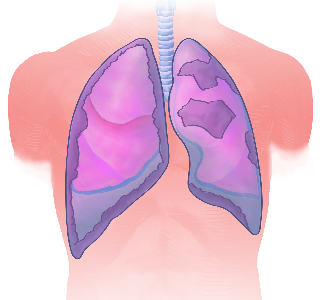

Detailreiche Fotografien aus der medizinischen Praxis ergänzen die Texte; moderne, genaue,

wissenschaftliche Zeichnungen geben Einblick in die Anatomie und die Funktion der Lunge und

anderer Organe.